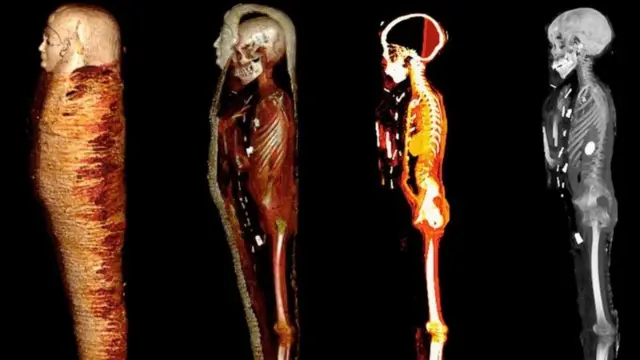

ஒரு நூற்றாண்டுக்கும் மேலாக இந்த உடல் வல்லுநர்களால் முழுமையாக ஆய்வு செய்யப்படாமல் இருந்த நிலையில், கெய்ரோ பல்கலைக்கழகத்தைச் சேர்ந்த சஹர் சலீம் தலைமையிலான குழு சிடி ஸ்கேனரை பயன்படுத்தி மம்மியை ஆய்வு செய்தபோது இந்த உண்மை தெரியவந்துள்ளது.

ஆனால், தற்போதுள்ள கம்ப்யூட்டட் டோமோகிராஃபி (computed tomography) நுட்பம், மம்மிகளை சேதப்படுத்தாமல் ஆய்வு செய்ய ஒரு சிறந்த கருவியாக மாறும் என்றும், இது பண்டைய கால மனிதர்களின் ஆரோக்கியம், நம்பிக்கைகள் மற்றும் திறன்கள் குறித்து கூடுதலாக ஆராயவும் உதவும் என்கிறார் சலீம்.

"கம்ப்யூட்டட் டோமோகிராஃபி கதிரியக்க துறையில் ஏற்பட்ட குறிப்பிடத்தக்க முன்னேற்றத்தைக் காட்டுகிறது. ஒரு படத்தைப் பயன்படுத்துவதற்குப் பதிலாக, இதன் மூலம் உடலின் சிறு பகுதிகளின் நூற்றுக்கணக்கான கணிப்புகளை ஒன்றிணைத்து முழுமையான முப்பரிமாண மாதிரியை உருவாக்க முடியும்" என்றும் சலீம் கூறுகிறார்.